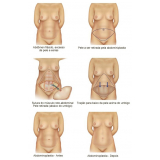

Abdominoplastia com Lipo

Há momentos em que é necessário ter por perto profissionais qualificados e dedicados à pronta recuperação do paciente. A FF Cirurgia Plástica oferece e coloca à sua disposição o que existe de mais atualizado em procedimento cirúrgico para abdominoplastia com lipo. Com o objetivo de levar qualidade à vida dos clientes, a instituição oferece infraestrutura adequada às necessidades de cada um: cuidado médico humanizado, realizado através de dedicação, profissionalismo e amor.

Você precisa de um consultório médico que realize abdominoplastia com lipo com segurança!